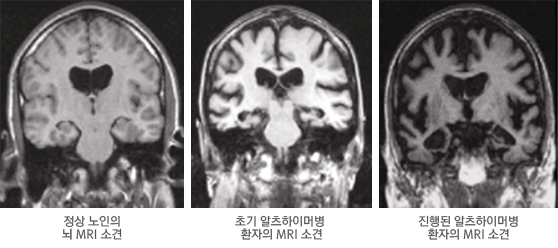

알츠하이머병 진단에 있어 환자에 대해 가장 잘 알고 있는 보호자의 보고를 통한 정확한 병력 청취가 매우 중요하다. 의사는 이전에 비해 기억력을 포함한 인지 기능의 변화가 있는지, 있다면 언제부터 어떠한 양상으로 나타났는지 확인하고, 신체검사와 신경학적 검사, 정신상태 검사, 일상생활 기능수준 검사, 혈액 검사 등의 실험실 검사, 뇌영상학검사, 신경심리검사 등을 통해 진단을 내린다. 1. 신체검사와 신경학적 검사 환자의 인지 기능에 영향을 줄 수 있는 신체질환 및 뇌신경계 질환의 징후가 있는지 진찰한다. 2. 정신상태 검사 기억력 등의 인지기능을 평가하고 섬망이나 혼돈과 같은 의식의 장애가 있는지, 우울증이나 망상, 환각 등의 동반된 정신행동증상이 있는지를 평가한다. 3. 일상생활동작 검사 일상생활에서의 기능수준이 어느 정도인지를 평가한다. 식사하기, 옷 입기, 씻기, 대소변 가리기 등의 기본적인 일상생활과 전화하기, 음식물 만들기, 돈 관리하기 등과 같은 좀 더 복잡한 일상생활동작에 대해 평가한다. 이러한 검사는 진단을 위한 평가뿐만 아니라 향후 환자 관리에도 도움을 줄 수 있는 기본적인 정보가 된다. 4. 혈액 검사 등의 실험실 검사 치매 상태를 초래할 수 있는 여러 신체질환을 파악하기 위해 빈혈검사, 간기능검사, 신기능검사, 당뇨검사, 비타민검사, 갑상선기능검사, 지질검사, 흉부 X레이, 심전도, 소변검사 등 다양한 실험실 검사를 시행한다. 5. 뇌 영상검사 뇌 영상검사는 자기공명영상(MRI), 컴퓨터단층촬영(CT) 등 구조적 뇌 영상검사와 양자방출단층촬영(PET), 단일광자방출촬영(SPECT) 등 기능적 뇌 영상검사로 구분된다. MRI와 CT는 뇌의 구조나 모양을 살펴보기 위한 검사로 알츠하이머병에서 나타나는 뇌의 위축, 뇌실 확대 등 뇌의 구조적 이상 소견을 확인할 수 있다. 근래에는 CT보다 해상도가 높은 MRI를 널리 사용한다. 알츠하이머병에서는 MRI 검사상 특징적인 내측두엽 위축 소견이 비교적 초기 단계에서부터 확인되는 경우가 흔하다. PET이나 SPECT와 같은 기능적 뇌 영상검사를 시행하면 뇌의 혈류량 또는 뇌의 포도당 대사능력 등을 측정함으로써 뇌 각 부위의 기능 이상을 확인할 수 있다. 구조적 뇌 영상검사에서 별다른 이상이 나타나지 않는 초기 알츠하이머병의 경우에도 이러한 기능적 뇌 영상검사로 뇌 기능의 저하 여부와 저하 부위(측두엽 및 두정엽 대사 저하)를 조기에 확인할 수 있어 조기 진단에 매우 유용하다. 검사 정확도에 있어 PET이 SPECT보다 우수하여 기능적 뇌 영상검사가 필요한 경우 PET 사용이 권고된다. 최근 알츠하이머병의 핵심 병리인 아밀로이드 판 등 베타아밀로이드 단백질 응집 상태 자체를 영상화 할 수 있는 리간드들도 개발되어 사용되고 있다. 대표적인 아밀로이드 PET 영상 리간드로 11C-Pittsburg Compound B(PIB)가 있다. 6. 신경심리검사 신경심리검사는 뇌 기능과 관련된 다양한 인지기능을 객관적으로 정밀하게 평가하는 검사이다. 신경심리 검사에는 기억력, 언어능력, 주의집중력, 판단능력, 계산능력, 수행능력, 시공간파악능력 등 다양한 인지영역에 대한 광범위한 평가가 포함된다. 신경심리검사 결과를 통해 어떤 영역의 인지기능이 어느 정도 수준으로 저하되었는지에 대한 객관적 정보를 얻을 수 있으며, 이러한 정보는 치매 여부의 진단이나 원인 감별에 참고자료로 활용된다. 또한 치료 시작 전 신경심리검사를 통해 환자의 기저 인지기능 수준에 대한 정보를 미리 얻어 둠으로써 향후 치료 효과 파악을 위한 기준으로 활용할 수 있다.

알츠하이머병 MRI 영상